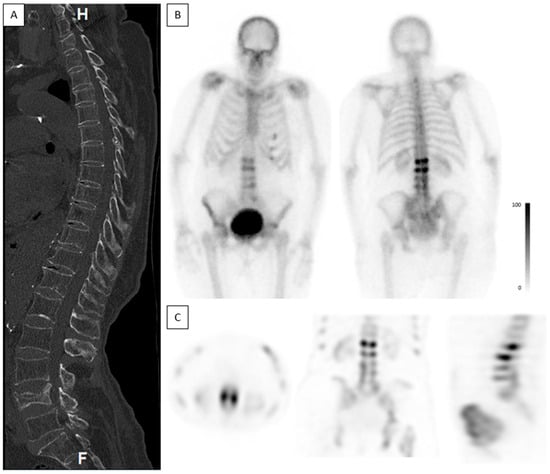

Figure 5. Occult fractures. A 78-year-old female complaining of back pain, without known trauma. CT was acquired on the day of admission and bone scintigraphy was performed 2 days after the CT. (A)—Sagittal spine CT shows a non-union fracture in L4. No other fractures are demonstrated. Bone density measured in L3 was 7 HUs, consistent with severe osteoporosis. (B)—Planar anterior and posterior bone scintigraphy shows high-intensity uptake in L2 and L3, suggestive of acute fractures. (C)—Axial, coronal, and sagittal SPECT show high-intensity uptake in L2 and L3.